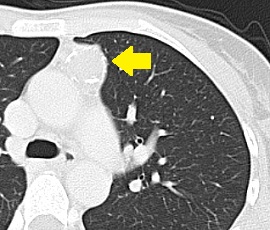

[胸腺腫] 手術:胸腔鏡下縦隔腫瘍手術

CT画像